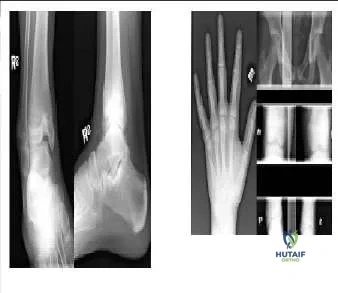

Question 20:

The radiograph (Slide 1) of an 11-year-old boy with significant leg pain is presented. No other abnormalities are found during the patientâ s history or physical examination. The most likely diagnosis is:

Correct Answer: Fibrous dysplasia

Explanation:

Fibrous dysplasia is chronically expansile with vague transition to normal bone and a â ground-glassâ appearance. These characteristics differentiate fibrous dysplasia from aneurysmal and unicameral bone cysts. Additionally, the lack of periosteal reaction differentiates fibrous dysplasia from malignancy or osteomyelitis. The patients magnetic resonance image (Slide 2) is also provided.